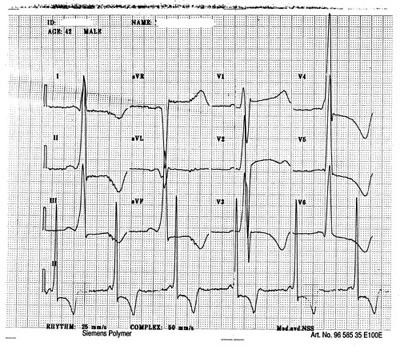

Pasient 2. Bror av pasient 1. 35 år gammel fikk han tilfeldig påvist betydelige elektrokardiografiske tegn til venstre ventrikkel-hypertrofi. PQ-tid var normal (120 ms). Ekkokardiografi viste en generell hypertrofi av venstre ventrikkel, mest uttalt i apex cordis og laterale vegg. Det var god systolisk funksjon og ingen intraventrikulær gradient. Pasienten har hatt anfall med kortvarige palpitasjoner fra sekunders til opptil ett minutts varighet. Båndspiller-EKG har påvist korte løp med atrieflimmer. For øvrig har han ikke hatt kardiale symptomer. Blodtrykket har vært normalt. Han ble fulgt ekkokardiografisk i 2 – 3 år under diagnosen hypertrofisk kardiomyopati av ukjent genese inntil hans bror fikk diagnostisert Fabrys sykdom. Det ble da påvist betydelig redusert alfagalaktosidaseaktivitet i isolerte leukocytter fra blod (1,68 µ kat/kg protein, referanseområde 17,7 – 26,4 µ kat/kg) ) og betydelig økt urinutskilling av globotriaosylceramid (140 µ mol/mol kreatinin, referanseområde<10 µ mol/mol) og diheksosid (135 µ mol/mol kreatinin, normalt bare spormengder) – de substansene som ikke metaboliseres ved Fabrys sykdom. Pasienten har normal nyrefunksjon. Det kom etter hvert frem at han alltid har vært plaget med kalde hender og føtter og at han lett blir irritert i øynene. Oftalmologisk undersøkelse har vist lette epiteliale avleiringer i cornea samt bilateral lett bakre kortikal katarakt, forandringer typiske for Fabrys sykdom. Etter at diagnosen ble stilt, har han vært fulgt i ca. tre år med uendrede kardiale funn.